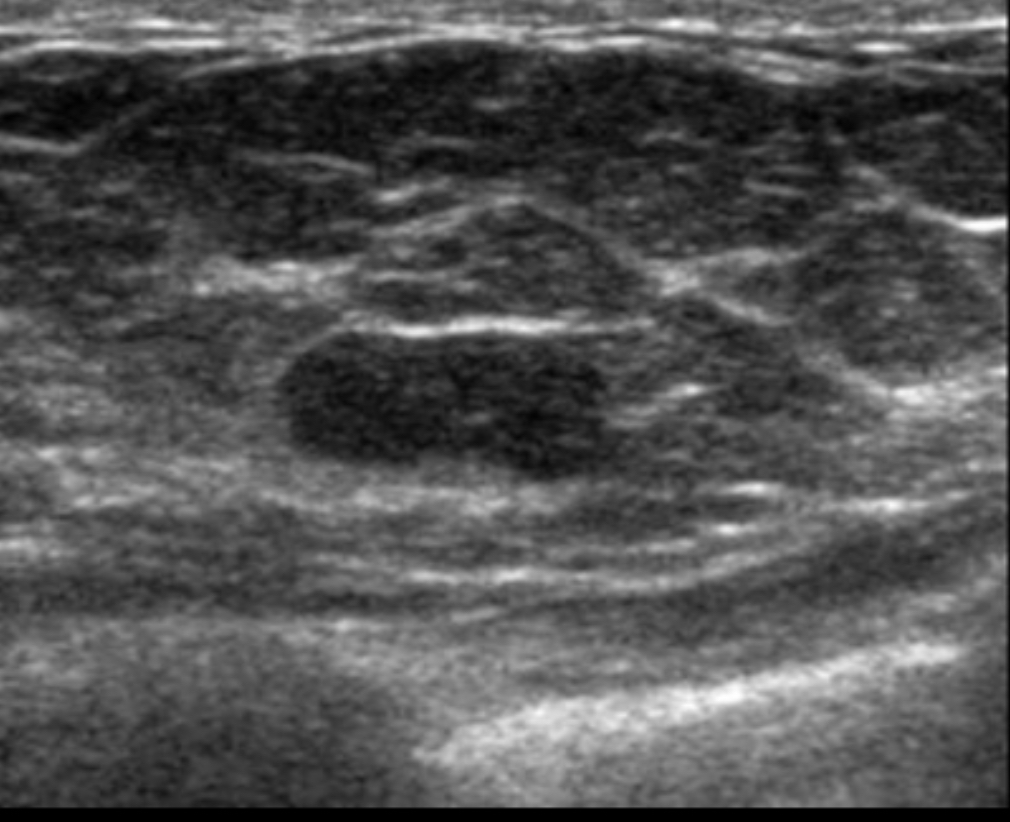

What BIRADS

BIRADS 3

an oval, circumscribed, nonpalpable mass on a baseline mammogram constitutes 1 of the accepted BI-RADS 3 (probably benign) lesions.

Others:

focal asymmetry that becomes less dense on spot compression view

cluster of punctate calcifications